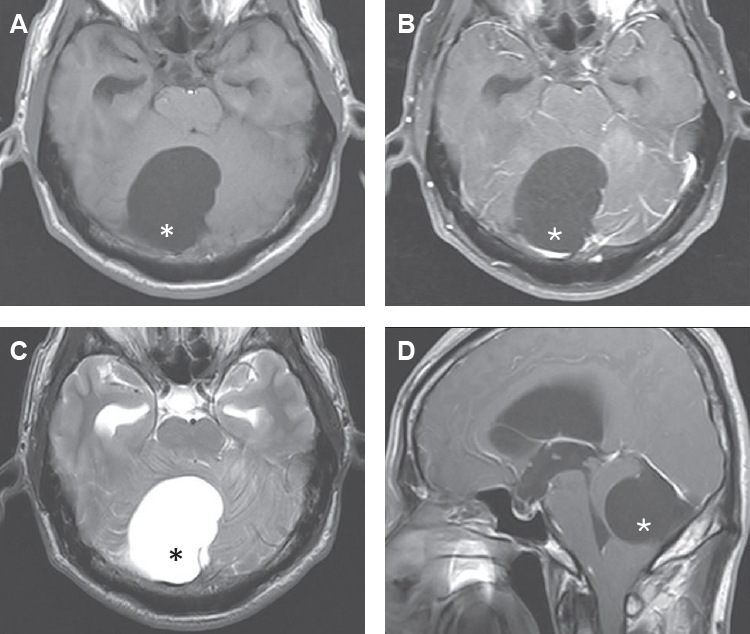

A fatal case of complex hepatic alveolar echinococcosis

Li Xin, Li Mengmeng, Yu Huixia, Zan Runna, Li Guojun, Shang Rongjian, Yu Jia

Parasites Hosts Dis 2026;64(1):98-103.

Published online January 22, 2026

DOI: https://doi.org/10.3347/PHD.25022

Hepatic alveolar echinococcosis (HAE), a life-threatening zoonosis, poses formidable surgical challenges when involving critical vasculature. Herein, we reported the periprocedural management dilemmas in radical resection for advanced HAE. A 58-year-old female visited the outpatient department presented with HAE. Imaging examination revealed extensive invasion of the hilum, bile duct, and several hepatic vessels, as well as left adrenal metastasis. The patient underwent right trisegmentectomy with left hepatic vein reconstruction, auto-transplantation, and adrenalectomy, with intraoperative Doppler demonstrating patent portal flow before abdominal closure. However, emergency thrombectomy and transcatheter thrombolysis were performed due to the abrupt occurrence of portal vein thrombosis 3 h after surgery. Despite intervention, the residual liver volume remained insufficient (approximately 28% of the standard liver volume), leading to progressive liver failure. The patient expired from multiorgan failure 9 days after operation. This case underscores not only the critical balance between radical resection and preservation of residual liver function in the surgical management of complex HAE, but also the imperative need to establish a comprehensive postoperative thromboprophylaxis.